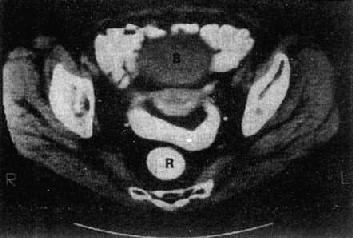

子宫体在CT上易于识别,显示为横置的密度较高的梭形影像,CT值40~80Hu,宫体中央密度可略低。子宫大小受年龄和生理状态的影响,一般成人前后径为1.5~3cm,左右径为3~5cm,老年人子宫较小。膀胱充盈程度也影响子宫的大小。子宫前方为膀胱,呈液性低密度;后方为直肠,内常有气体。膀胱、子宫、直肠之间常有肠袢存在。宫颈在宫体下方层面,呈卵圆形软组织影。卵巢位于子宫侧壁和臼内壁之间,正常大小时CT常不见。增强扫描,子宫密度均匀增加,膀胱内造影剂为高密度,盆腔内血管输尿管显示为高密度,易于识别(图4-5-5)。

图4-5-5 女性盆腔正常CT表现

子宫呈横行的梭形软组织影(↓),其前方为膀胱(B)

其后方、骶骨之前为直肠(R)